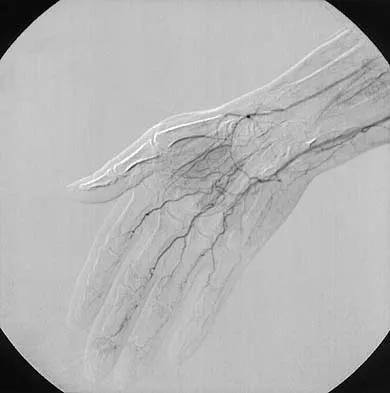

The condition shown in Figures 9a and 9b is most likely the result of

The clinical photograph and radiograph show gout, which is the result of urate deposition in the joint and soft tissues. Radiographs frequently reveal periarticular erosions. The crystals are intracellular and negatively birefringent under the polarized microscope. Treatment for acute flares include colchicines, indomethacin, and corticosteroids (including injections). Medications such as allopurinol help prevent recurrent flares. Tophi such as that seen in this patient are often confused with and associated with infection. Wortmann RL, Kelley WM: Crystal-induced inflammation: Gout and hyperuricemia, in Harris ED, Budd RC, Firestein GS, et al (eds): Kelley's Textbook of Rheumatology, ed 7. New York, NY, Elsevier Science, 2005, pp 1402-1429. Trumble TE (ed): Hand Surgery Update 3: Hand, Elbow, & Shoulder. Rosemont, IL, American Society for Surgery of the Hand, 2003, pp 433-457.